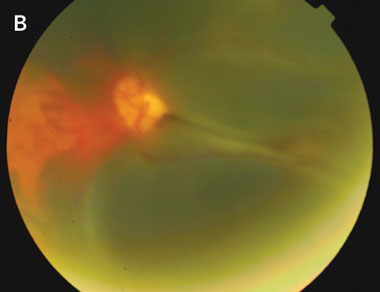

B: Fundus photograph of the left eye at the time of presentation of visual loss in this eye. Extensive subretinal haemorrhage is seen in the macula. Again, the haziness of the photograph is indicative of vitreous haemorrhage. |

Development of large subretinal and vitreous haemorrhages in neovascular AMD is uncommon. Treatment options are limited and, even with surgical intervention, visual outcomes are in the range of light perception to counting fingers only, with significant loss of paracentral and peripheral vision.4 The functional effects are therefore profound.

In our patient, the role of concurrent aspirin therapy is unclear, as there is no evidence in the literature to support or refute the hypothesis that concurrent antiplatelet therapy may have contributed to the development of haemorrhage. However, both instances of haemorrhage were noted to occur at times when his INR was high compared with those recorded over the previous 12 months. Our patient was taking aspirin at all times during this period. Although it is possible that intraocular haemorrhage may have occurred purely as a result of his underlying neovascular AMD, the temporal relationship between the development of the haemorrhages and the high INRs strengthens the case for the implication of warfarin therapy as a contributing factor. Application of the Naranjo probability scale7 indicates that this adverse drug event was probable (Naranjo score, + 5).

The association between anticoagulant therapy and intraocular haemorrhage is of key importance for several reasons. Firstly, massive intraocular haemorrhage is an important diagnosis to consider in an anticoagulated patient who presents with loss of vision, and who has a background of neovascular AMD. Secondly, patients with neovascular AMD in one eye are at risk of developing neovascular AMD in the second eye,8 and therefore at risk of developing large intraocular haemorrhages in both eyes if long-term anticoagulation is continued.